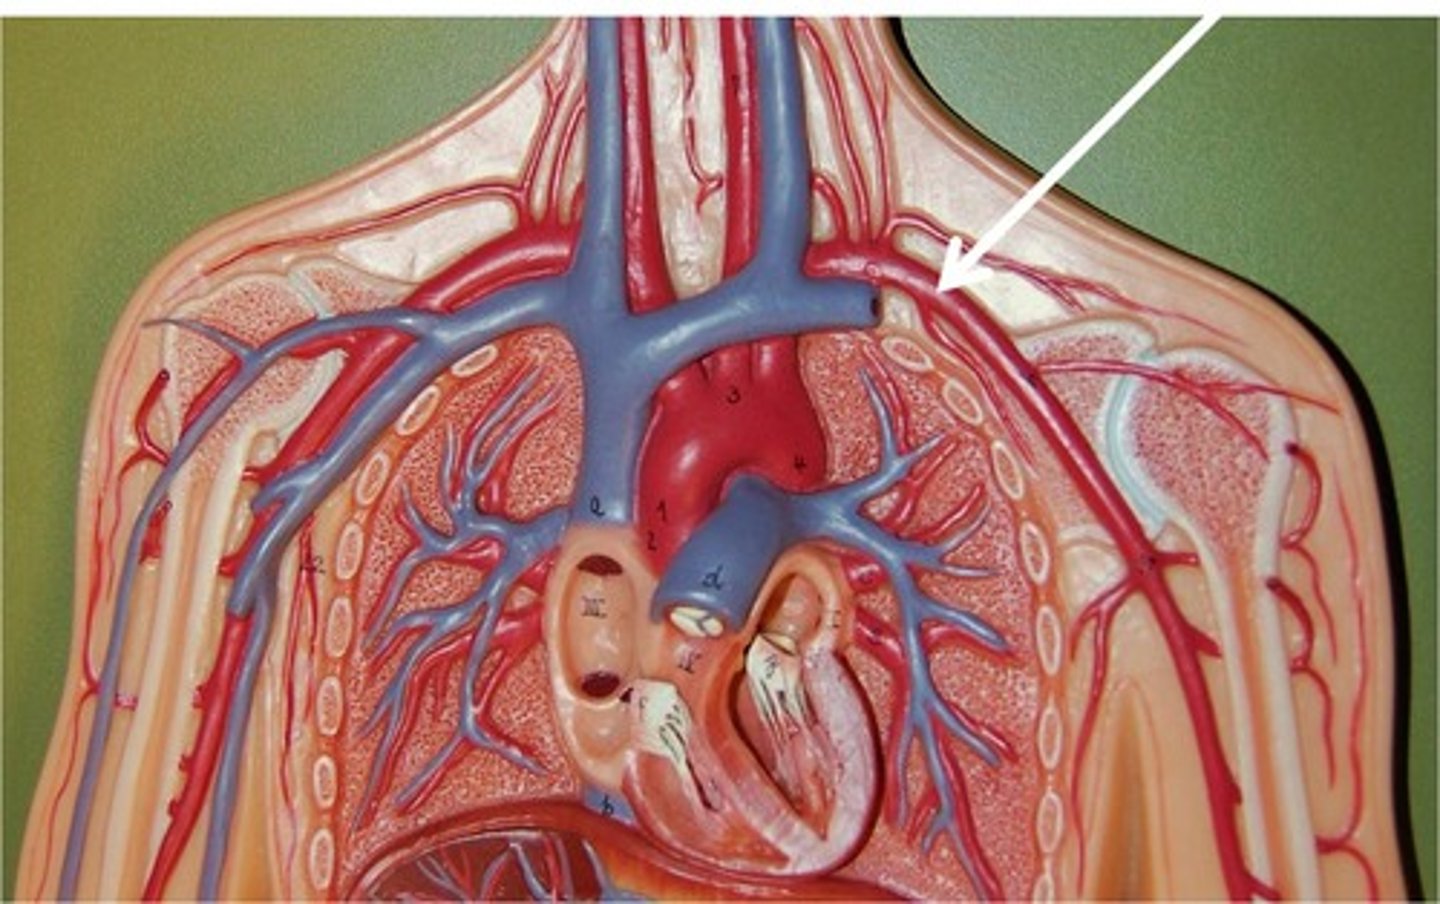

brachiocephalic artery

st

flat tube before curve on top of heart

9

R common carotid artery

medial split off brachiocephalic artery

10

R subclavian artery

lateral split off brachiocephalic artery, goes under clavicle

11

L common carotid artery

2nd split off arch

left subclavian artery

3rd split off arch, goes directly left

leftmost tube of aorta